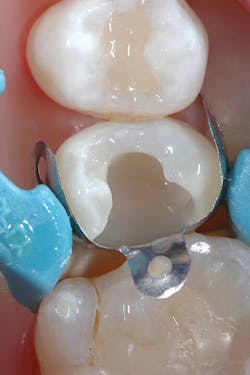

Although the bulk-fill flowable can be placed in larger increments, a small increment was placed first to ensure sufficient curing of the material at the floor of the chamber (figures 3 and 4). The next layer of SureFil SDR flow+ was placed in a 4-mm bulk increment again, followed by 20 seconds of light curing. A final layer of universal composite was placed, occlusion was checked, and after a final polish and postoperative radiograph, the patient was released (figures 5 and 6).